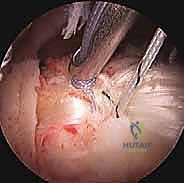

في هذا الدليل الطبي المرجعي والشامل، سنتعمق بشكل غير مسبوق في فهم اعتلال والتهاب وتر العضلة ذات الرأسين. سنبدأ بتشريحه المعقد الذي يجعله عرضة للإصابة، مروراً بالمسببات البيوميكانيكية، وعوامل الخطر، والأعراض السريرية المميزة. وصولاً إلى استعراض شامل لأحدث خيارات التشخيص والعلاج المتاحة عالمياً. وسنركز بشكل مكثف على تقنيات "العلاج بالمنظار الجراحي"، والذي يمثل الثورة الأهم في جراحة الكتف الحديثة، موفراً حلولاً جذرية وفعالة بحد أدنى من التدخل الجراحي.

بصفتنا خبراء رواد في جراحة العظام، المفاصل، والطب الرياضي، فإننا نؤمن إيماناً راسخاً بأهمية التثقيف الطبي وتزويد المرضى بالمعلومات الدقيقة، الموثوقة، والشاملة لتمكينهم من اتخاذ قرارات مستنيرة وواثقة بشأن صحتهم. وفي هذا السياق الطبي المتقدم، يبرز اسم الأستاذ الدكتور محمد هطيف في العاصمة صنعاء كمرجع علمي وطبي رائد في تشخيص وعلاج حالات الكتف الأكثر تعقيداً. بخبرة تتجاوز العشرين عاماً، ومكانة أكاديمية رفيعة كأستاذ في جامعة صنعاء، يسخر الدكتور هطيف أحدث التقنيات الجراحية بالمنظار لضمان استعادة المرضى لوظائفهم الحركية بأعلى درجات الأمان والنجاح.